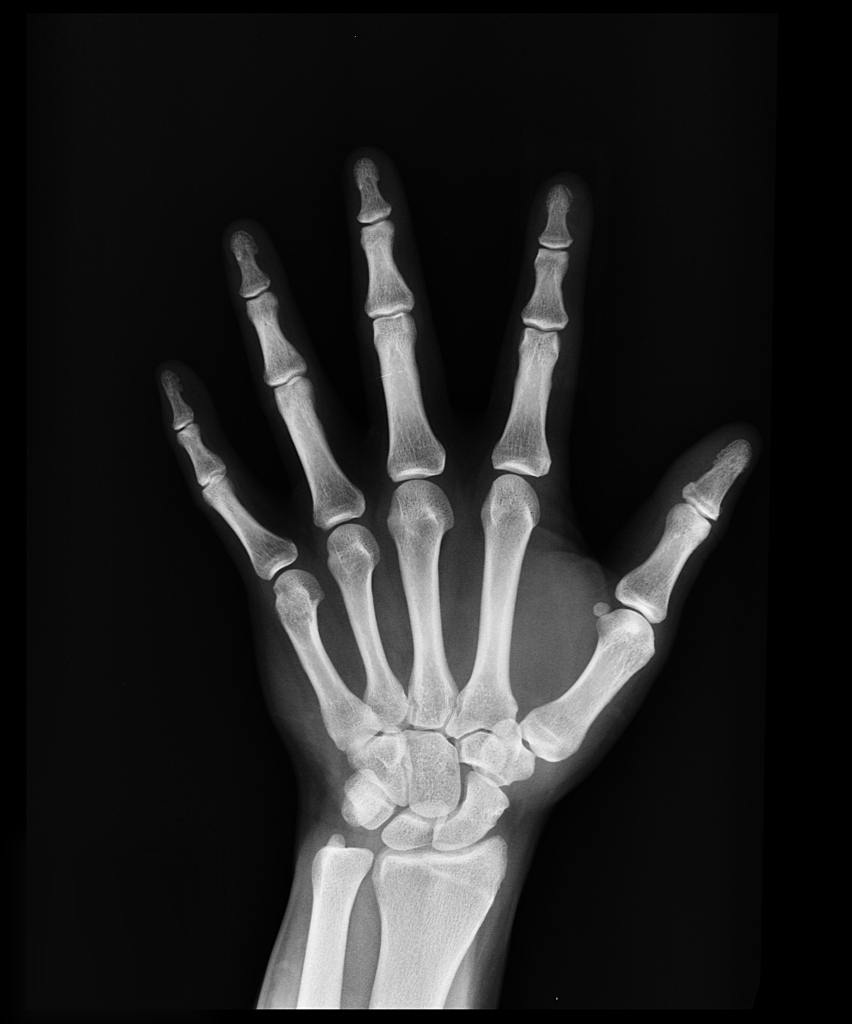

Measuring Bones in Micro-gravity

A major challenge facing astronauts is that living in a microgravity environment changes the body and, in particular, slows down bone cell growth. Consequently, while in space, their body reabsorbs old bone material faster than it makes new bone. This results in a net loss of bone mass or osteopenia. To counteract this, astronauts use specialized equipment that allows them to do weight-bearing exercises every day. They also take vitamin d, calcium, and sometimes additional supplements like bisphosphonate and teriparatide. However, most astronauts still lose between 1 and 2% of their bone mass every month that they’re on a space mission.

Consequently, NASA and other space travel groups are researching new ways to aggressively treat osteopenia and osteoporosis. One promising avenue – teaming up with private drug companies to test the effectiveness of newly developed osteoporosis drugs.

Traditionally, quantifying the effectiveness of osteoporosis drugs has been difficult. Such tests involve comparing the bone mass changes between a treatment group that receives the medicine and a control group that does not. However, activity levels also affect bone mass and can vary significantly within both groups. This makes it very hard to interpret the data and determine whether taking the drug had any positive effects.

However, in a microgravity environment differences in daily movement do not affect bone mass. This is a huge advantage – one big enough to encourage people to swallow the hefty price of carrying out tests aboard a rocket ship. Several osteoporosis drugs have now been tested in space. What to find out more? Read this article about how a now popular and mass-marketed drug was first tested aboard the space station in 2016 or this article about a potential new drug that not only slows bone growth but also speeds bone creation.